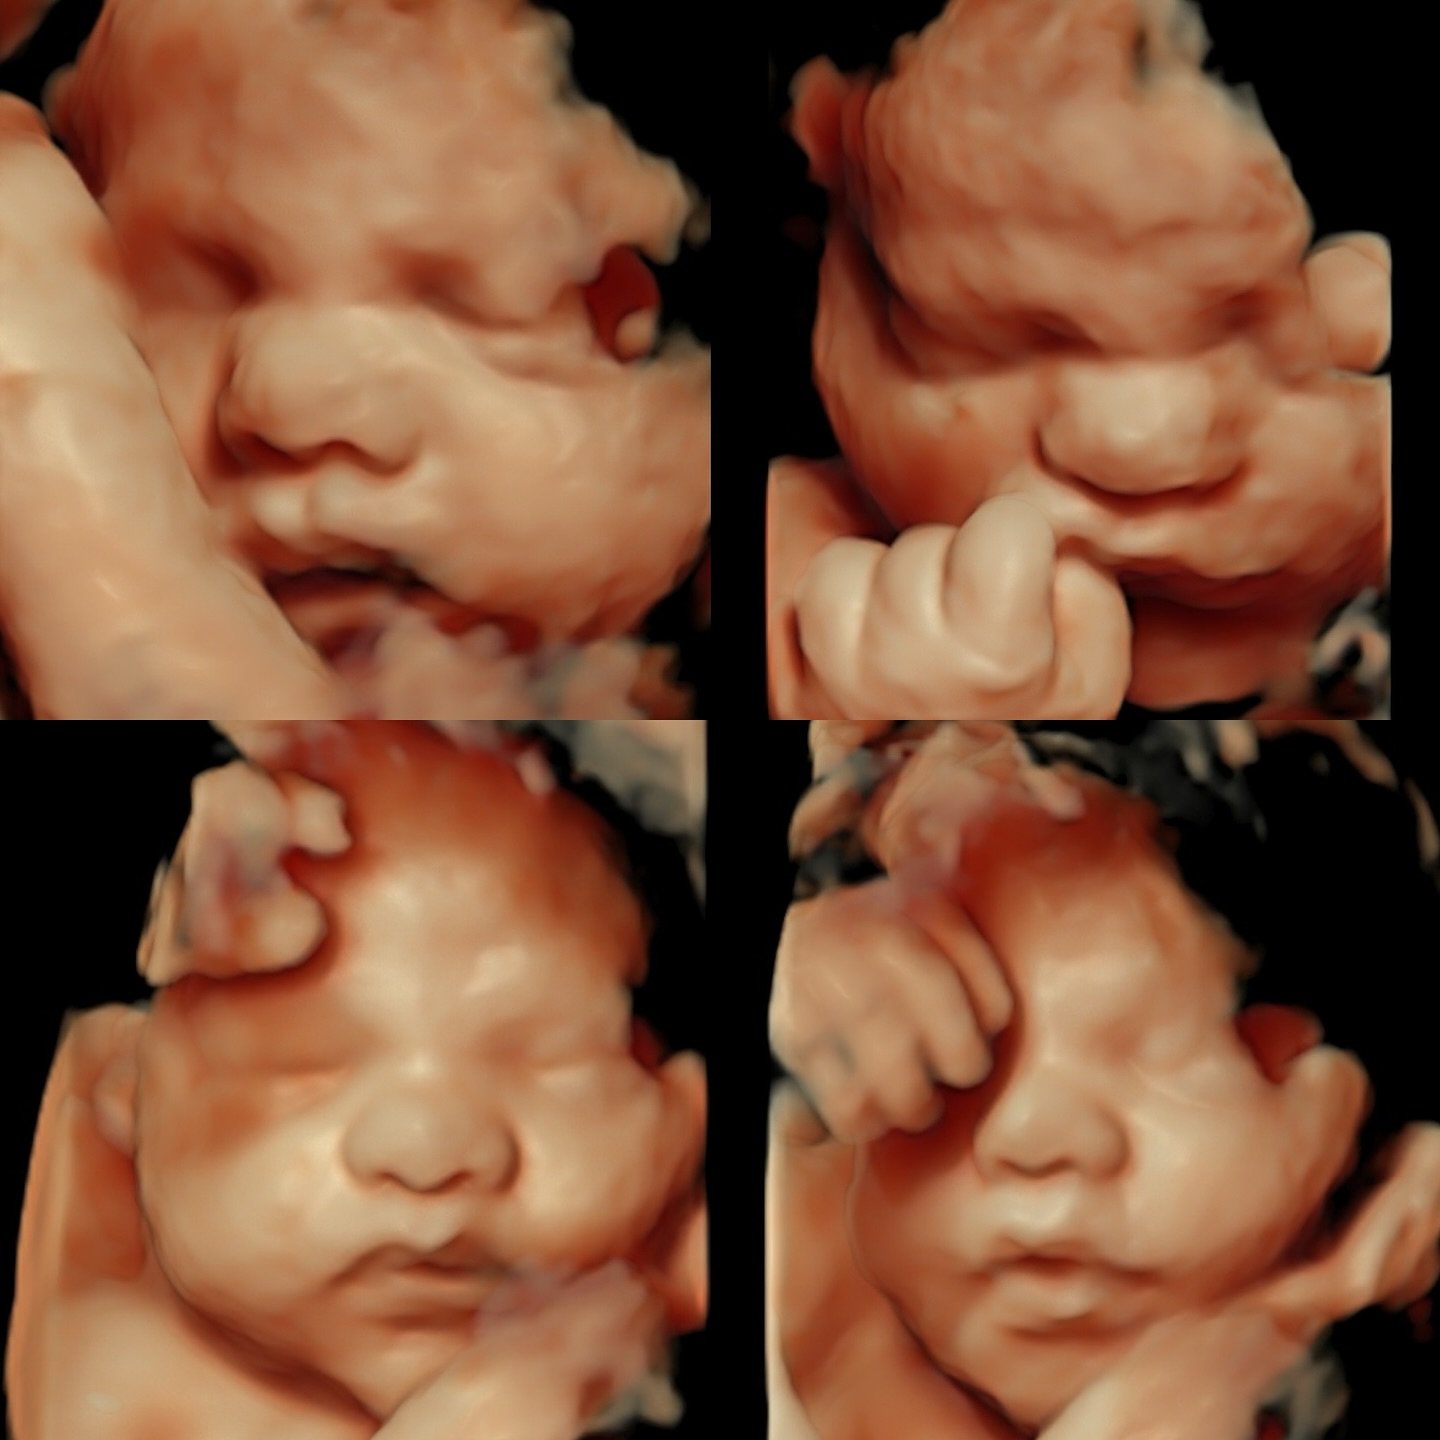

Welcome to Sentiments 4D Ultrasound Studio where beautiful memories begin. Our studio offers a warm, relaxing environment designed to make every visit special and stress-free. With over 10 years of professional ultrasound experience, you can trust that you’re in skilled and caring hands. From early heartbeat scans to breathtaking 3D/4D/HD live imaging, we’re here to help you connect with your baby in the most meaningful way.

In addition to elective ultrasounds, Sentiments offers comprehensive diagnostic obstetric and gynecologic imaging. Our scans are performed with precision, compassion, and attention to detail β€” ensuring you receive accurate results in a comfortable, stress-free environment.